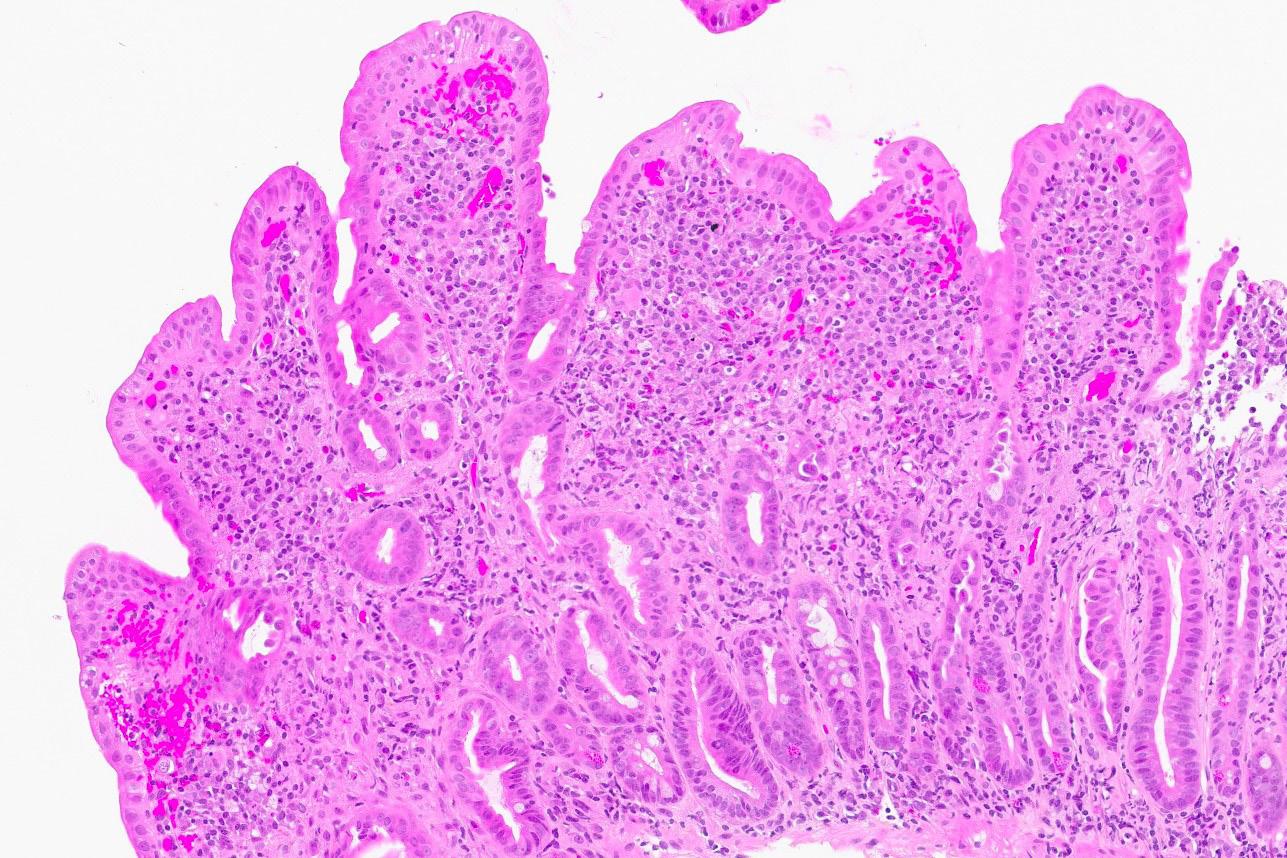

Det ble da også tatt biopsier fra terminale ileum, som viste moderat totteatrofi og kronisk betennelse. Duodenalbiopsi viste totteatrofi og økt antall intraepiteliale lymfocytter (bilde 1 og 2) tilsvarende cøliaki Marsh grad 3b. Anti-TG2 var negativ og hun hadde normal total IgA. MR av tynntarm viste normale forhold.

Bilde 1: (HES, 120x) Fra syk fase. Biopsi fra duodenum med uttalt totteatrofi, nærmest flat slimhinne. Blandet betennelsesinfiltrat i lamina propria (lymfocytter, plasmaceller, nøytrofile og eosinofile granulocytter) og økt antall lymfocytter i overflateepitelet.